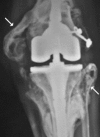

Today, total knee arthroplasty (TKA) is one the most commonly performed surgeries worldwide. The purpose of this article is to review the appearance of normal post-TKA roentgenographs and describe the correct sequence for their interpretation. It is unwise to depend solely on patients' symptoms when diagnosing TKA complications because serial radiographs can foresee failures well before they manifest clinically. Ideal post-TKA radiographs comprise whole lower extremity anteroposterior and lateral views taken under weight bearing conditions along with a skyline view of the patellofemoral joint. Among other things, weight bearing exposes the true alignment, ligamentous laxity and polyethylene wear. On the basis of follow-up of our TKA cases, we have drawn up a protocol for assessing postoperative X-ray films after TKAs. Following the proposed sequence, surgeon can easily decide how to proceed with follow-up and foresee complications. Careful interpretation of postoperative radiographs after TKA is essential to careful monitoring of patients and implant survival.